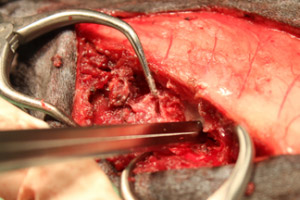

-

脊髄を露出し逸脱した椎間板を摘出しました。後は閉創し術式は以上で終了となります。 術後は約2ヶ月でほぼ以前と変わらず歩けるようになりました。飼い主様が熱心にリハビリをして頂いた結果、症状は重度でしたが無事完治することができてホッとしています。ミニチュアダックスは椎間板ヘルニアになる子が多く、予防としてソファーや階段などで自由に遊ばせないことが重要です。 今では元気に走り回ってます。